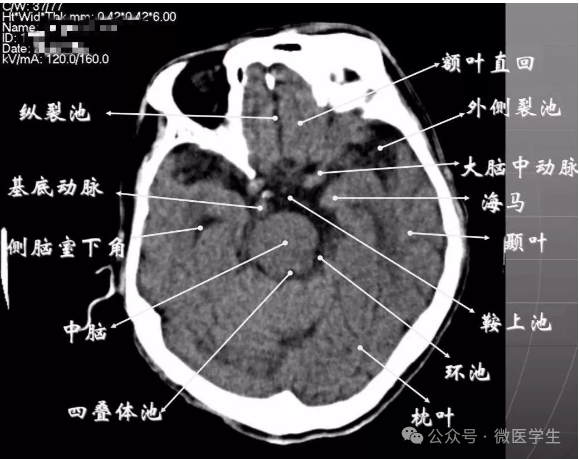

正常解剖

- 颅前窝底部:眼眶,眼球,筛窦,蝶窦,前床突等。

- 颅中窝:前界—蝶骨;后界—颞骨岩部(岩骨);内缘—海绵窦及垂体窝;外缘—颞骨,窝内为颞叶,其内侧为海马回。

- 颅后窝:前缘—岩骨;后缘—枕骨;鞍背后方—脑桥前池,向两侧延伸为脑桥小脑角池。

- 第四脑室:位于颅后窝中线上,后面紧邻小脑蚓部,其两侧为小脑扁桃体。

- 延髓、脑桥:位于第四脑室前。

- 颅前窝:颞叶。

- 鞍上池:在垂体窝上方,位于两侧颅中窝之间,前界为颞叶直回,侧方位颞叶海马,呈五角星形或六角星形。其前角连于纵裂池,两外侧角连于外侧裂池,两后外侧角延续于环池,第六个角位于后缘中间,是角间池。鞍上池边缘为大脑动脉环,池内前部常可见“v”字型视交叉。

- 颅后窝:四脑室或四叠体池。

显示侧脑室前角的下部:

- 前方—额叶;外侧—尾状核头部;后方中线处—第三脑室,其两侧连接丘脑。

- 基底核、丘脑。

- 内囊前脚(前肢);尾状核和豆状核之间。

- 内囊膝部和后脚(后肢):位于豆状核(由外侧的壳核和内侧的苍白球组成)及丘脑之间。

- 壳核的外侧:外囊、屏状核、最外囊、岛叶(脑岛)。

- 四叠体池:两侧枕叶之间,池内有松果体,向前与第三脑室连接。